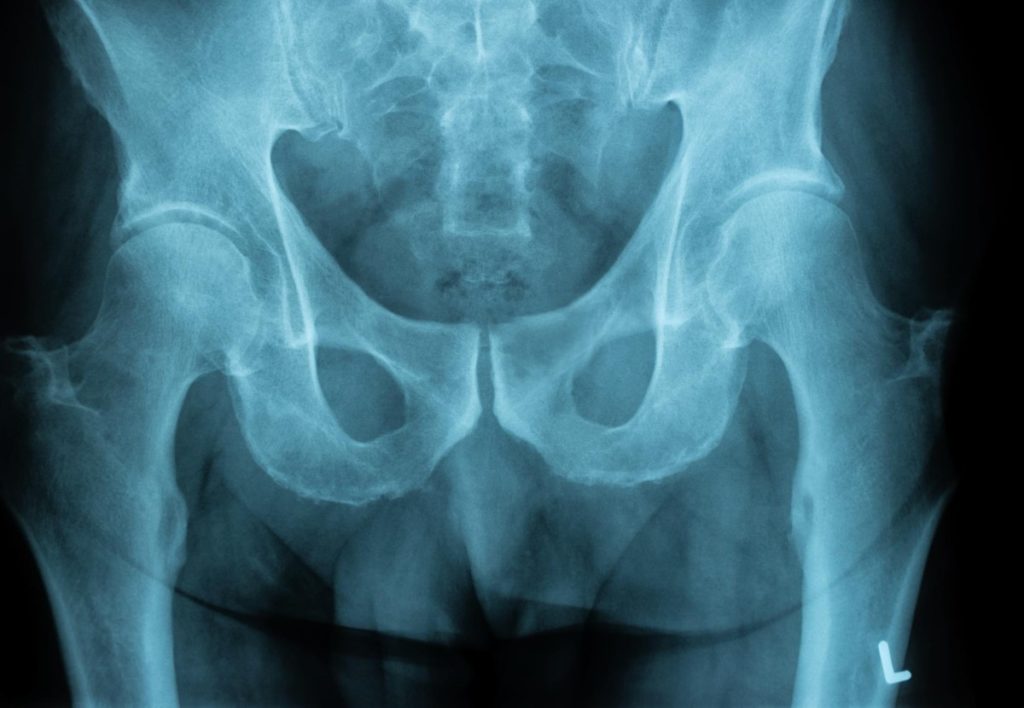

Na maioria das vezes sentir uma dor no quadril durante a corrida pode ser alguma afecção desencadeada por ausência de preparo ou aquecimento adequados. No geral, artrite, bursite, dores musculares e compressão nervosa são as causas mais comuns da dor no quadril. Porém em atletas, o impacto direto ou indireto e o uso excessivo da musculatura podem acarretar dores, lesões e queixas frequentes que vejo no consultório.

As dores no quadril e virilha são muitas vezes resultado de um estiramento do músculo adutor ou distensão muscular da origem do quadríceps. Diante disso, separei abaixo algumas das causas mais comuns de dor no quadril em atletas e como evitá-las:

1. Bursite trocanteriana – Uma das principais causas de dor na região lateral do quadril, a bursite trocanteriana é uma inflamação da bursa sinovial (uma bolsa repleta de fluido) localizada sobre o trocanter do fêmur com função de reduzir o atrito entre as estruturas (músculos, tendões e ossos) quando inflamada causa dor com o movimento do quadril.

Em corredores o uso excessivo da articulação está relacionada com o aparecimento dos sintomas, mas também pode ser provocada por queda ou impacto que resulta na inflamação da bursa do quadril. Em uma pancada/trauma direto o íleo um dos grandes ossos da pelve pode sofrer uma contusão e o atleta terá dor durante quase todo o movimento do quadril, resultando em limitação de movimento e interrupção da atividade. O tratamento pode ser eficaz, mas os sintomas podem ser persistentes, portanto não hesite em procurar ajuda médica.

1. fratura por estresse – Ocorre pelo desbalanço entre o desgaste( sobrecarga) e a regeneração óssea, principalmente em corredores de longa distância. É uma lesão decorrente do número repetitivo de movimentos localizados onde há uma sobrecarga óssea, resultando em micro-traumas no trabeculado osseo.  É mais comum em mulheres do que em homens e está associada a nutrição deficiente, distúrbios alimentares e endocrinológicos. Manter uma alimentação adequada e respeitar os limites e sinais do corpo é fundamental para evitar esse tipo de lesão. Como outros tipos de fraturas ósseas, deve-se permitir que o osso cicatrize, evitando exercícios e atividades de impacto.

1. Lesão labral – o labrum do quadril também chamado de lábio do acetábulo é uma braçadeira de tecido grosso (fibrocartilagem) que cerca a articulação do quadril. Ele confere estabilidade ao quadril. Quando ocorre uma lesão no lábio do acetábulo, um pedaço deste tecido pode se soltar ou apenas estar lesionado na articulação causando dor e sensações dolorosas ou estalos articulares.

1. Pubalgia – É uma lesão comum em corredores de longa distância, causada por esforço repetitivo na região da sínfise púbica ou na origem da musculatura adutora. Isso ocorre porque acima do osso púbis se inserem os músculos abdominais e abaixo do púbis se inserem os músculos adutores da coxa, assim, a dor na pelve pode irradiar para as coxas e abdômen. A ultrassonografia da região inguinal permite verificar o nível de rarefação óssea e fazer o diagnóstico diferencial com as hérnias. Pode ocorrer degeneração óssea, cisto, arrancamento e fraturas de estresse nos estágios avançados devido ao desequilíbrio muscular, chegando até a necrose óssea.

1. Subluxação – subluxação de quadril é uma lesão caracterizada pela saída parcial da cabeça do fêmur do acetábulo (empurrado parcialmente para fora da articulação) e está sendo reconhecido como uma possível causa de dor em atletas. A luxação completa da articulação de quadril é uma lesão muito incomum – ocorrem mais em acidentes automobilísticos de alta velocidade.

1. Artrite/artrose do quadril – É o chamado “desgaste” da articulação do quadril, atletas mais velhos ou que praticam esportes que geram sobrecarga na articulação podem experimentar rigidez e dor nas articulações, como resultado de artrite de quadril. A osteoartrite é uma das causas mais comuns de dor crônica do quadril para os atletas e não-atletas também. A osteoartrite é causada por desgaste ou degeneração das cartilagens do quadril. Ao longo do tempo, a  cartilagem que envolve a articulação se desgasta expondo a superfície óssea, gerando dor e limitação à movimentação. Há muitos tratamentos disponíveis, incluindo exercícios de fortalecimento apropriados, mas quando os tratamentos conservadores falham, a cirurgia de substituição (prótese) pode ser uma opção.